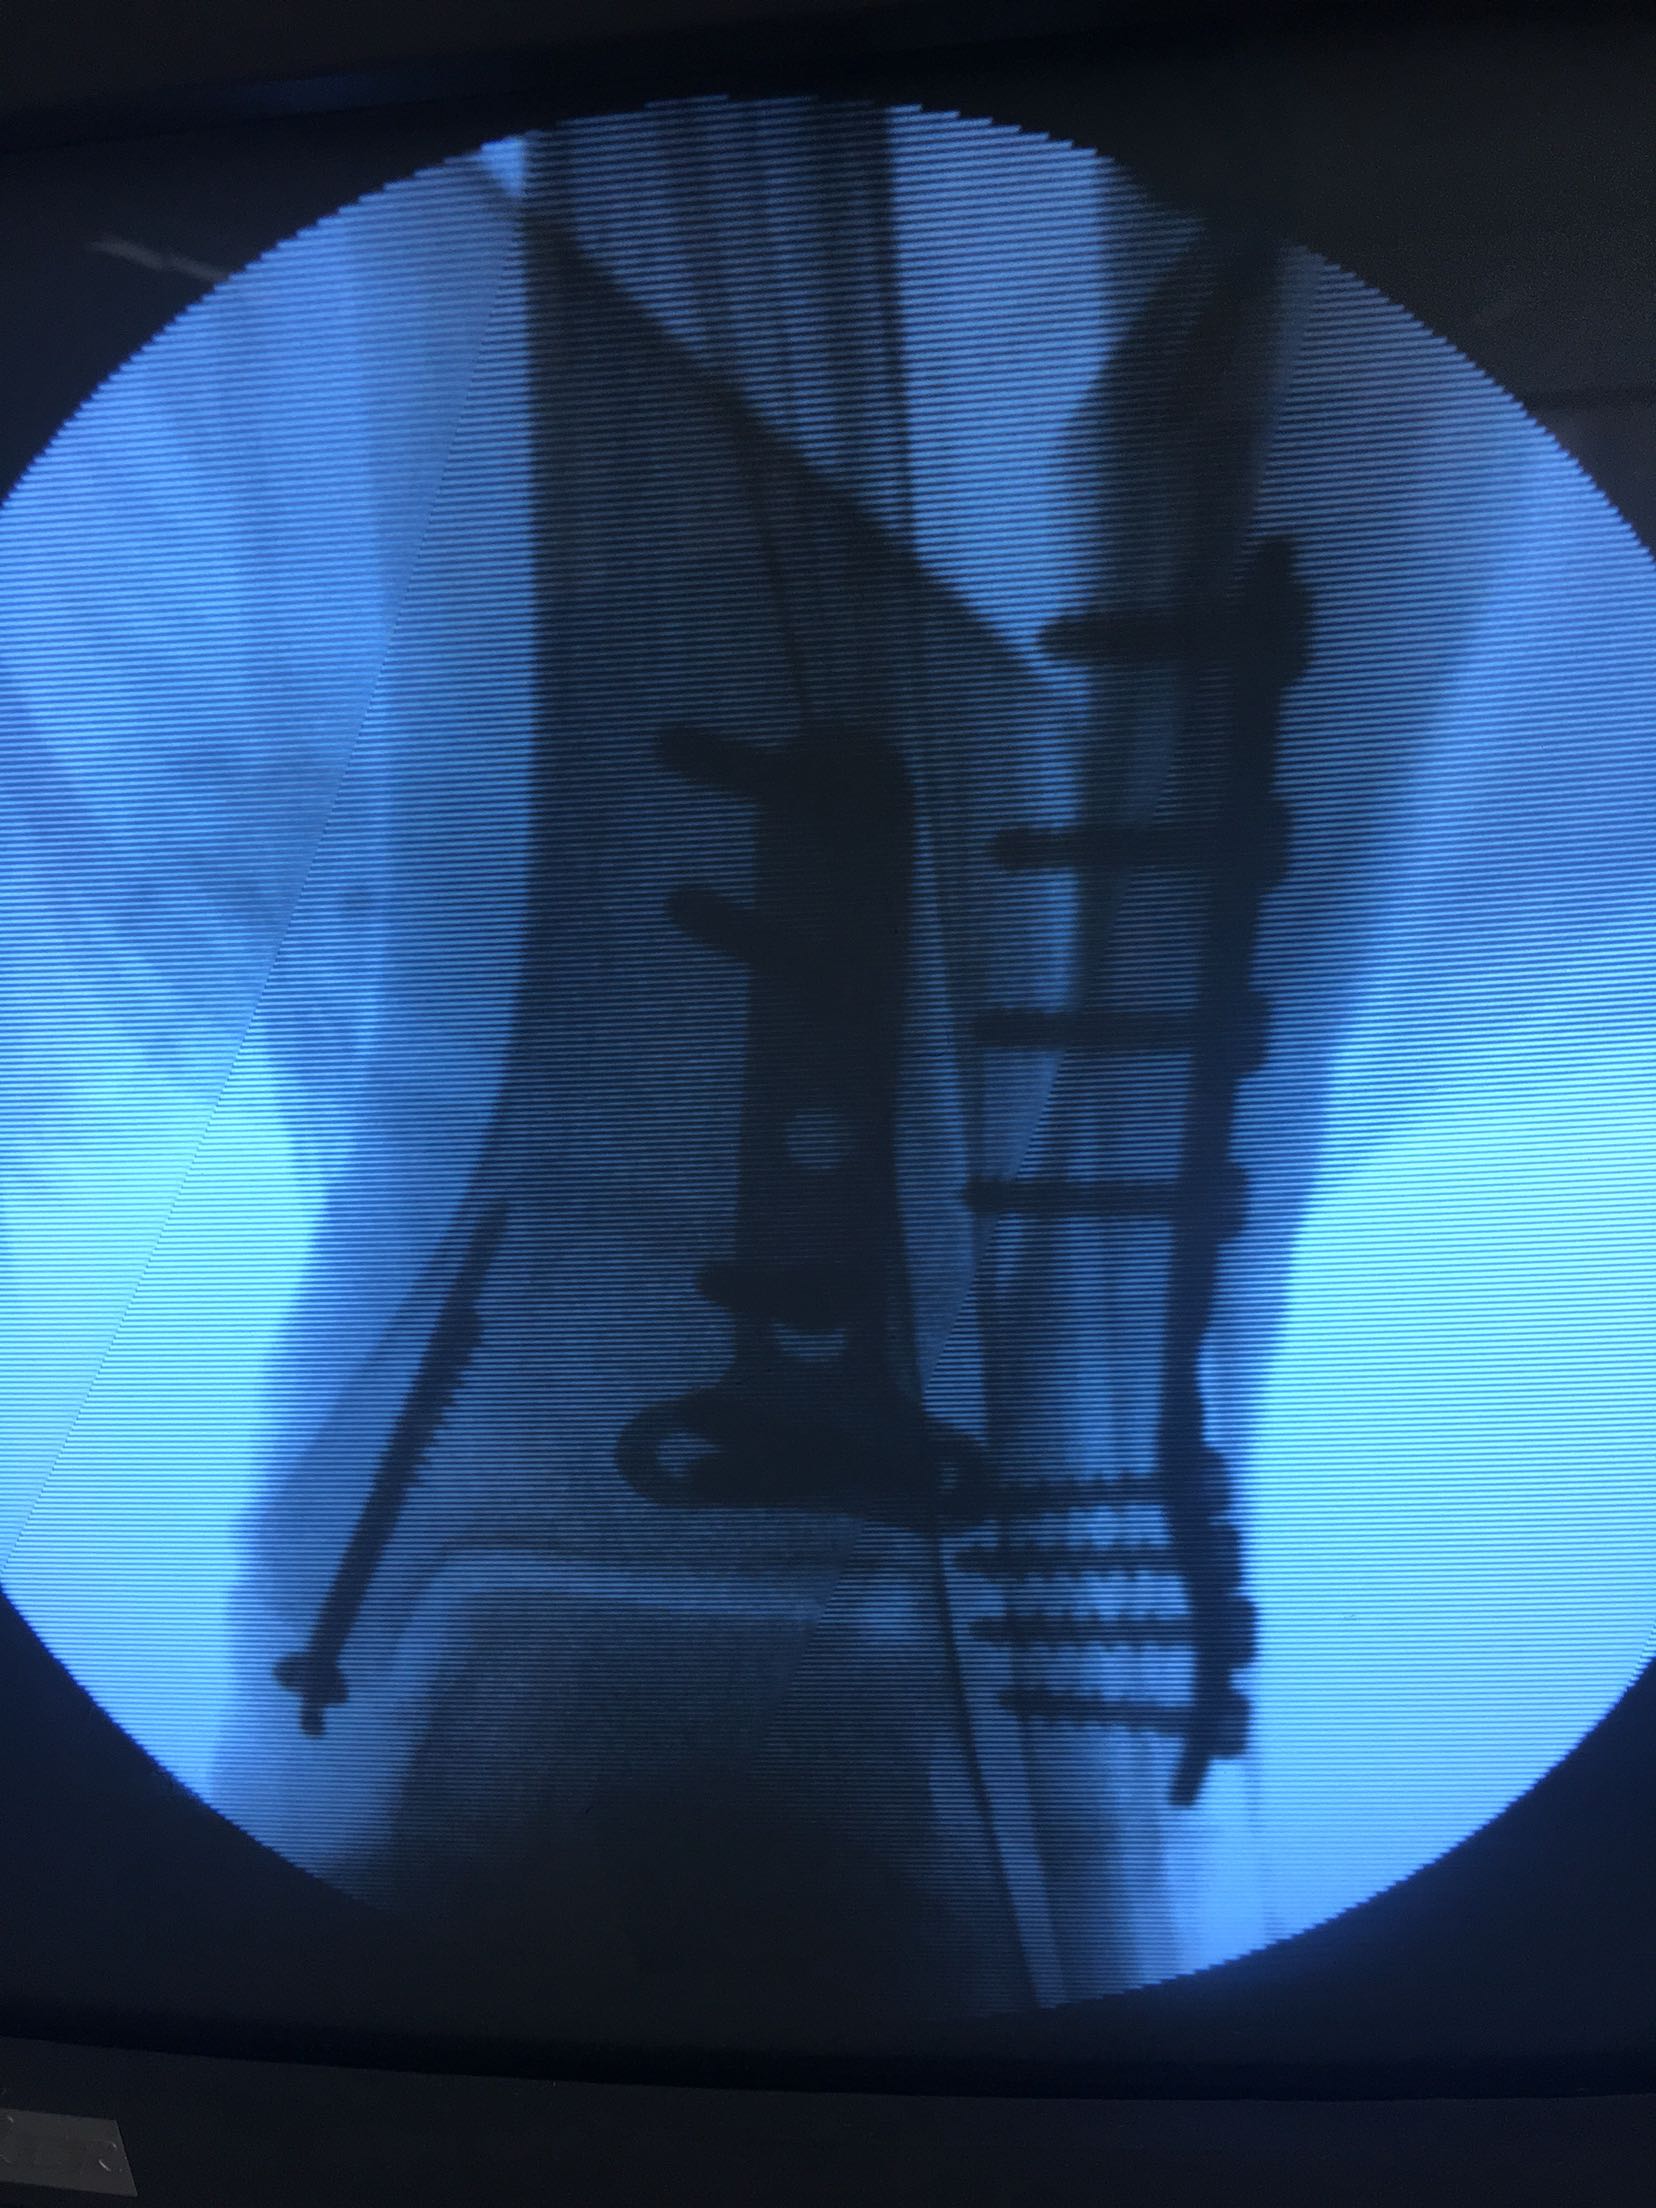

三踝粉碎性骨折(切复内固定)

急诊行跟骨结节牵引,术后一周肿胀消退,在腰麻下行切复内固定术,术后制动抬高,抗炎,消肿等对症处理。